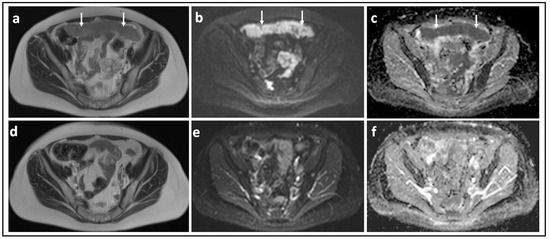

Figure 2.

Borderline versus malignant ovarian tumor: T2-W image (a) and corresponding b = 1000 s/mm2 DW-MRI (b) and ADC map (c) through the mid-pelvis in a patient with a mucinous borderline tumor of the left ovary. There is a large multiloculated cystic mass with no significant solid components (arrows). Two small foci of low signal in (b) show no evidence of diffusion restriction in c (arrowheads). In comparison, the T2-W image (d), b = 900 s/mm2 DW-MRI (e), and ADC map (f) in a patient with invasive high grade serous ovarian cancer show bilateral solid irregular ovarian masses (arrows) and linear peritoneal metastases [arrowheads], all of which show marked diffusion restriction.